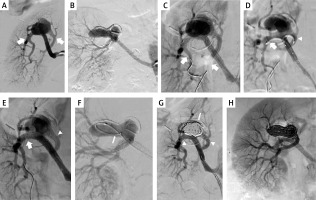

Figure 1

Patient 1. A – left renal artery aneurysm in the anterior-posterior projection; A1 – the scheme of aneurysm and the localisation of renal artery branches; r – renal artery, m – main branch, s – side branch, a – aneurysm; B – guidewires navigated to the distal segment of main branch (arrows point guidewire in the main and side branches; guidewire follows the curvature of aneurysm; arrowhead points guidewire in the main branch); C – successful reposition of guidewire in the side branch (arrow: guidewire in the side branch, prepared for stent introduction; arrowhead: guidewire in the main branch); D – successful navigation of the stent to the side branch (arrowhead), arrow points guidewire in the main branch; E – both stents are introduced and ready for expansion (arrow: stent in the side branch, arrowhead: stent in the main branch); aneurysm in this picture is seen from a different angle, in order to better visualize the stents; F – stent in the side branch has been expanded, it is properly positioned; G – aneurysm filled with coils, good inflow to the main branch (arrowhead); H – aneurysm filled with coils, good inflow to the side branch (arrowhead); guidewire is still inside the side branch (arrow)

First, we navigated a 6F/45 cm introducer sheath into the proximal part of the renal artery. Then, we introduced two 0.014” guidewires. The first one was introduced to the distal part of the main branch, and the second one – carefully, following the curvature of the aneurysm – to the distal part of the side branch (Figure 1 B). Even if it was possible to introduce the stent to the side branch, the stent was still blocked by the opposite wall of the aneurysm and its repositioning was not feasible. Therefore, we withdrew the stent and introduced a 2.5/20 mm MINI TREK Coronary Dilatation Catheter (Abbott Vascular, Abbott Park, IL, USA), which was inflated to the pressure of 6 atm, which allowed for a favourable reposition of the guidewire (Figure 1 B). Thereafter, over this guidewire, we introduced a 3 × 28 mm Xience stent (Abbott Vascular, Abbott Park, IL, USA) into the side branch, and then a 4 × 38 mm Xience stent to the main branch. The final position of the stents is shown in Figure 1 E. Once the proper position of the stents was obtained, we expanded the stent in the side branch with a balloon at a pressure of 11–20 atm. Then, the stent in the main branch was expanded under a pressure of 10–24 atm. Through the stent struts we introduced a Progreat microcatheter (Terumo, Tokyo, Japan) to the aneurysm, and using this microcatheter we filled its sac with 6 embolisation coils. Control arteriography demonstrated good inflow to the main and side branches, and complete closure of the aneurysm with coils (Figures 1 G, H).